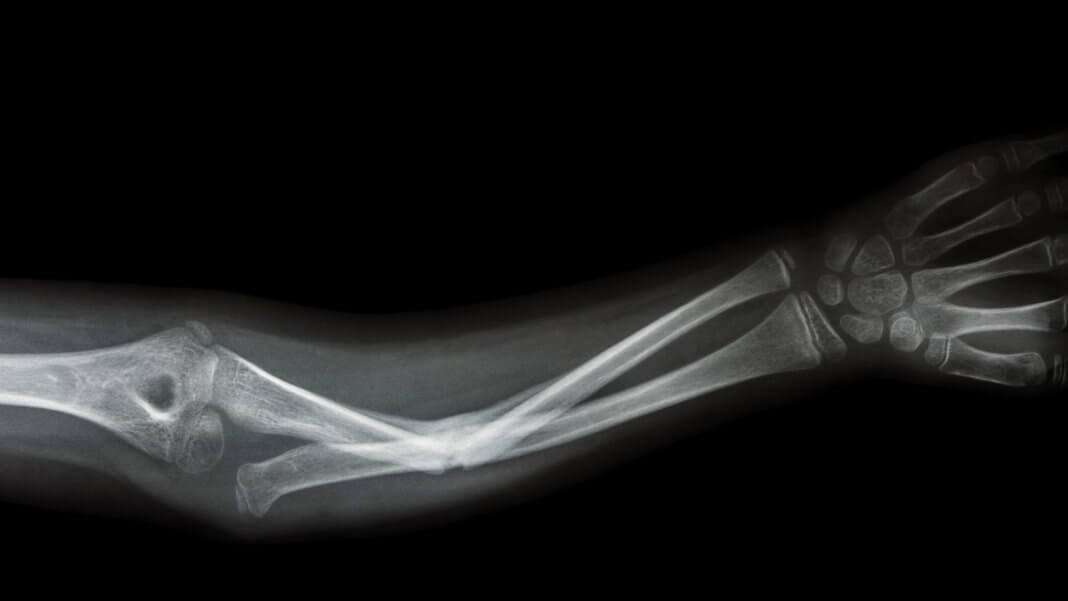

Когда вы были ребенком, вы когда-нибудь подписывались за одноклассника, если тот сломал руку или ногу? Носили за ним портфель? Сломанные кости для ребенка — очень плохо: несколько катастрофических секунд, за которыми следуют месяцы скучного отдыха и восстановления. Но у детей в будущем может быть другая история, поскольку новые технологии позволят нам пересмотреть, как мы восстанавливаем сломанные кости.

Краеугольный камень традиционной ортопедической медицины всегда заключался в том, чтобы обездвижить переломанные кости и позволить телу восстановиться. К счастью, наши тела прекрасно справляются с ремонтом костей; при правильной подгонке и достаточном времени, кости могут залечить даже очень серьезный урон, станут почти такими же хорошими, как новые.

Современные методы физическое терапии и методов восстановления улучшили этот подход «зафиксируй и забудь», добавив к нему активность, диету и покой, чтобы получить наилучшие результаты после сращения сломанных костей. Особо травматические случаи могут потребовать хирургических операций — установки штифтов, пластин и других конструкций, которые потребуют более продолжительного времени восстановления, большего объема физиотерапии, да и боли будет, откровенно говоря, больше. Возможности для улучшения процедур имеются в целом, но только в самых крайних случаях.